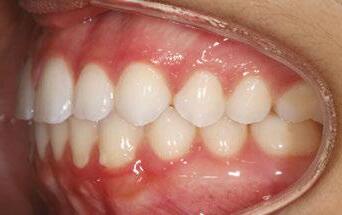

Figures 6 through 9 demonstrate a patient successfully treated with NiTime Aligners following the patient’s rejection of other systems. Figures 6 and 8 display pre- and posttreatment photos of a patient that presented with a Class II malocclusion and normal OB/OJ. This patient has teeth Nos. 7 and 10 missing congenitally. Note that the patient was treated as a child and has a canine substitution due to the missing lateral incisors. Recession was noted on tooth Nos. 2,3, 4, 5, 9, 11, 13, 14, 22, 24, 26, and 27. The patient tried labial and lingual brackets unsuccessfully, as well as a leading clear aligner to correct her malocclusion as an adult. In all three treatments, the patient could not tolerate the mechanics due to increased discomfort and was unable to complete therapy.

It is important to note that there was no refinement required for this case, and the patient finished in 26 weeks with 26 trays. Although the patient presented with significant recession, it did not worsen with treatment. As demonstrated in Figure 9, teeth aligned as planned by the OrthoFX treatment plan shown in Figure 7. Overlays of the actual results with the original treatment plan indicate a high level of predictive accuracy. Not only was a satisfactory result produced from the patient wearing the aligners, but the accuracy is quite high for the NiTime material despite the patient wearing it significantly less than the traditional 22 hours per day.

Figure 6: Class II malocclusion pretreatment

Figure 8: Class II malocclusion posttreatment. Left column pretreatment. Right column posttreatment 22 stages